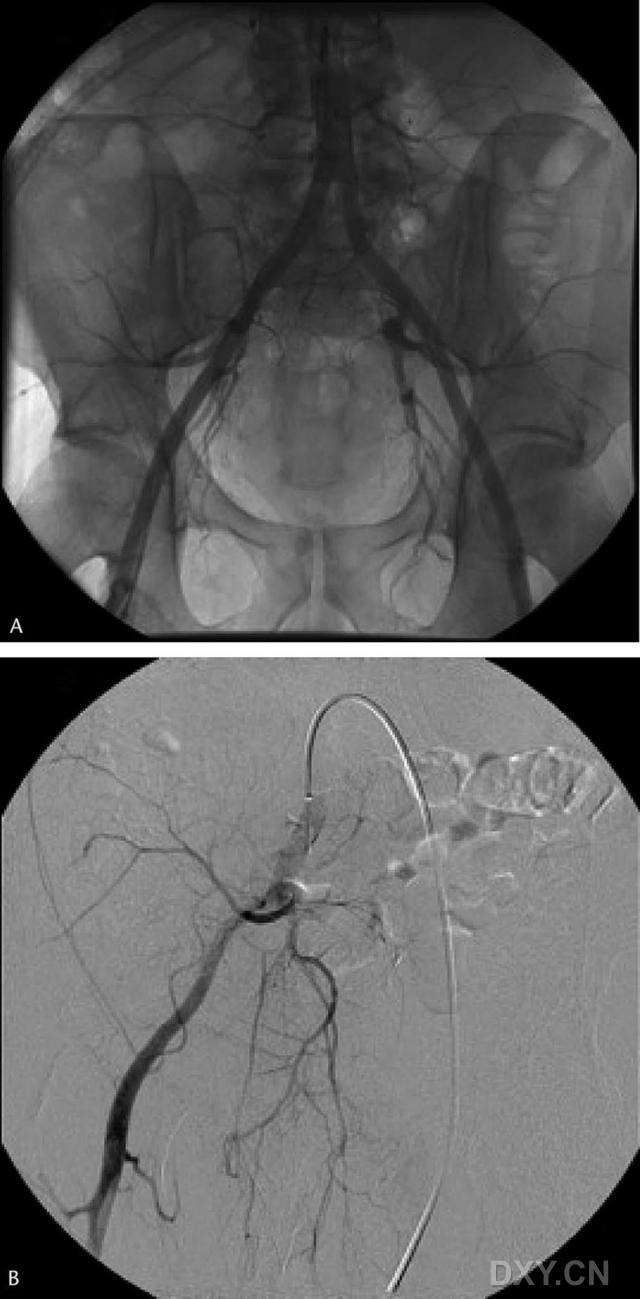

患者于术前即时在局部麻醉下行血管造影,经对侧腹股沟小皮肤切口进入,导丝穿刺进入股总动脉,将导管引导入腹主动脉远端后行血管造影检查。如无解剖变异,逐渐将导丝放入对侧(骨折侧)髂总动脉,行相关准备后再次血管造影,评估该侧骨盆及下肢的血运情况,其后将气囊放入髂总动脉略高于分支处,使气囊充满(图 1),并记录其容积,然后使气囊复原,固定各种置入装置及相关设备后将患者转运至手术室。

在手术室中进行常规术前准备,并在患侧下肢远端动脉内置导管以监测血流情况,手术开始后,由麻醉师负责血管内球囊的充起和还原,以 10 分钟为间隔,动脉导管主要用来监测血流的波形以及脉搏是否存在,而非测量压力,因为压力较容易受到静脉回流情况和患肢体位的影响。术后撤球囊和动脉导管,24 内每小时检查神经、血管功能情况,对患肢进行血氧监测。

通过与对照组的比较,应用 TPIIBO 组的患者失血量明显减少(图 2);实验组中,有 1 例 57 岁的男性患者发生髂总动脉血栓,术中麻醉医师发现了足背动脉的异常波形,且股动脉搏动触不到,行血管造影明确诊断后,由血管外科医师进行了血栓切开取出术。术后复查血管造影证实无血栓残留,患者术后进入血管外科重症监护室,后恢复良好。